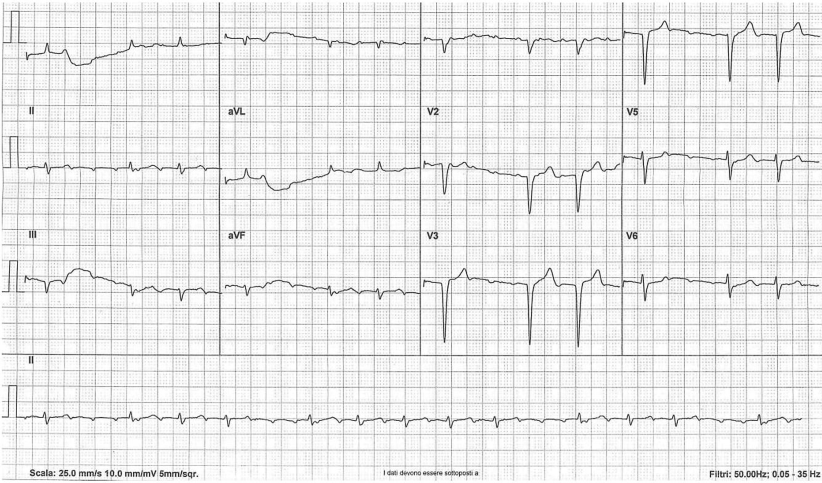

A 66-year-old male patient with a history of rheumatoid arthritis, coronary artery disease, hypothyroidism, end-stage renal disease and receiving haemodialysis presented to the emergency department with palpitations. His medication was acetylsalicylic acid, pantoprazole, levothyroxine, and paracetamol and ibuprofen as needed. Laboratory test results showed a mild anaemia and serum potassium levels within the upper limit of normal. A 12-lead electrocardiogram was recorded (Fig. 1). The electrocardiogram shows narrow QRS complexes (0.08 sec) with a QS morphology in leads V1 through V4 consistent with an old antero-septal wall myocardial infarction. The rhythm is irregular at an average rate of 79 beats per minute with groups of beatings separated by pauses. However, the underlying rhythm is not a sinus rhythm.

Fig. 1

The irregular atrial tachycardia